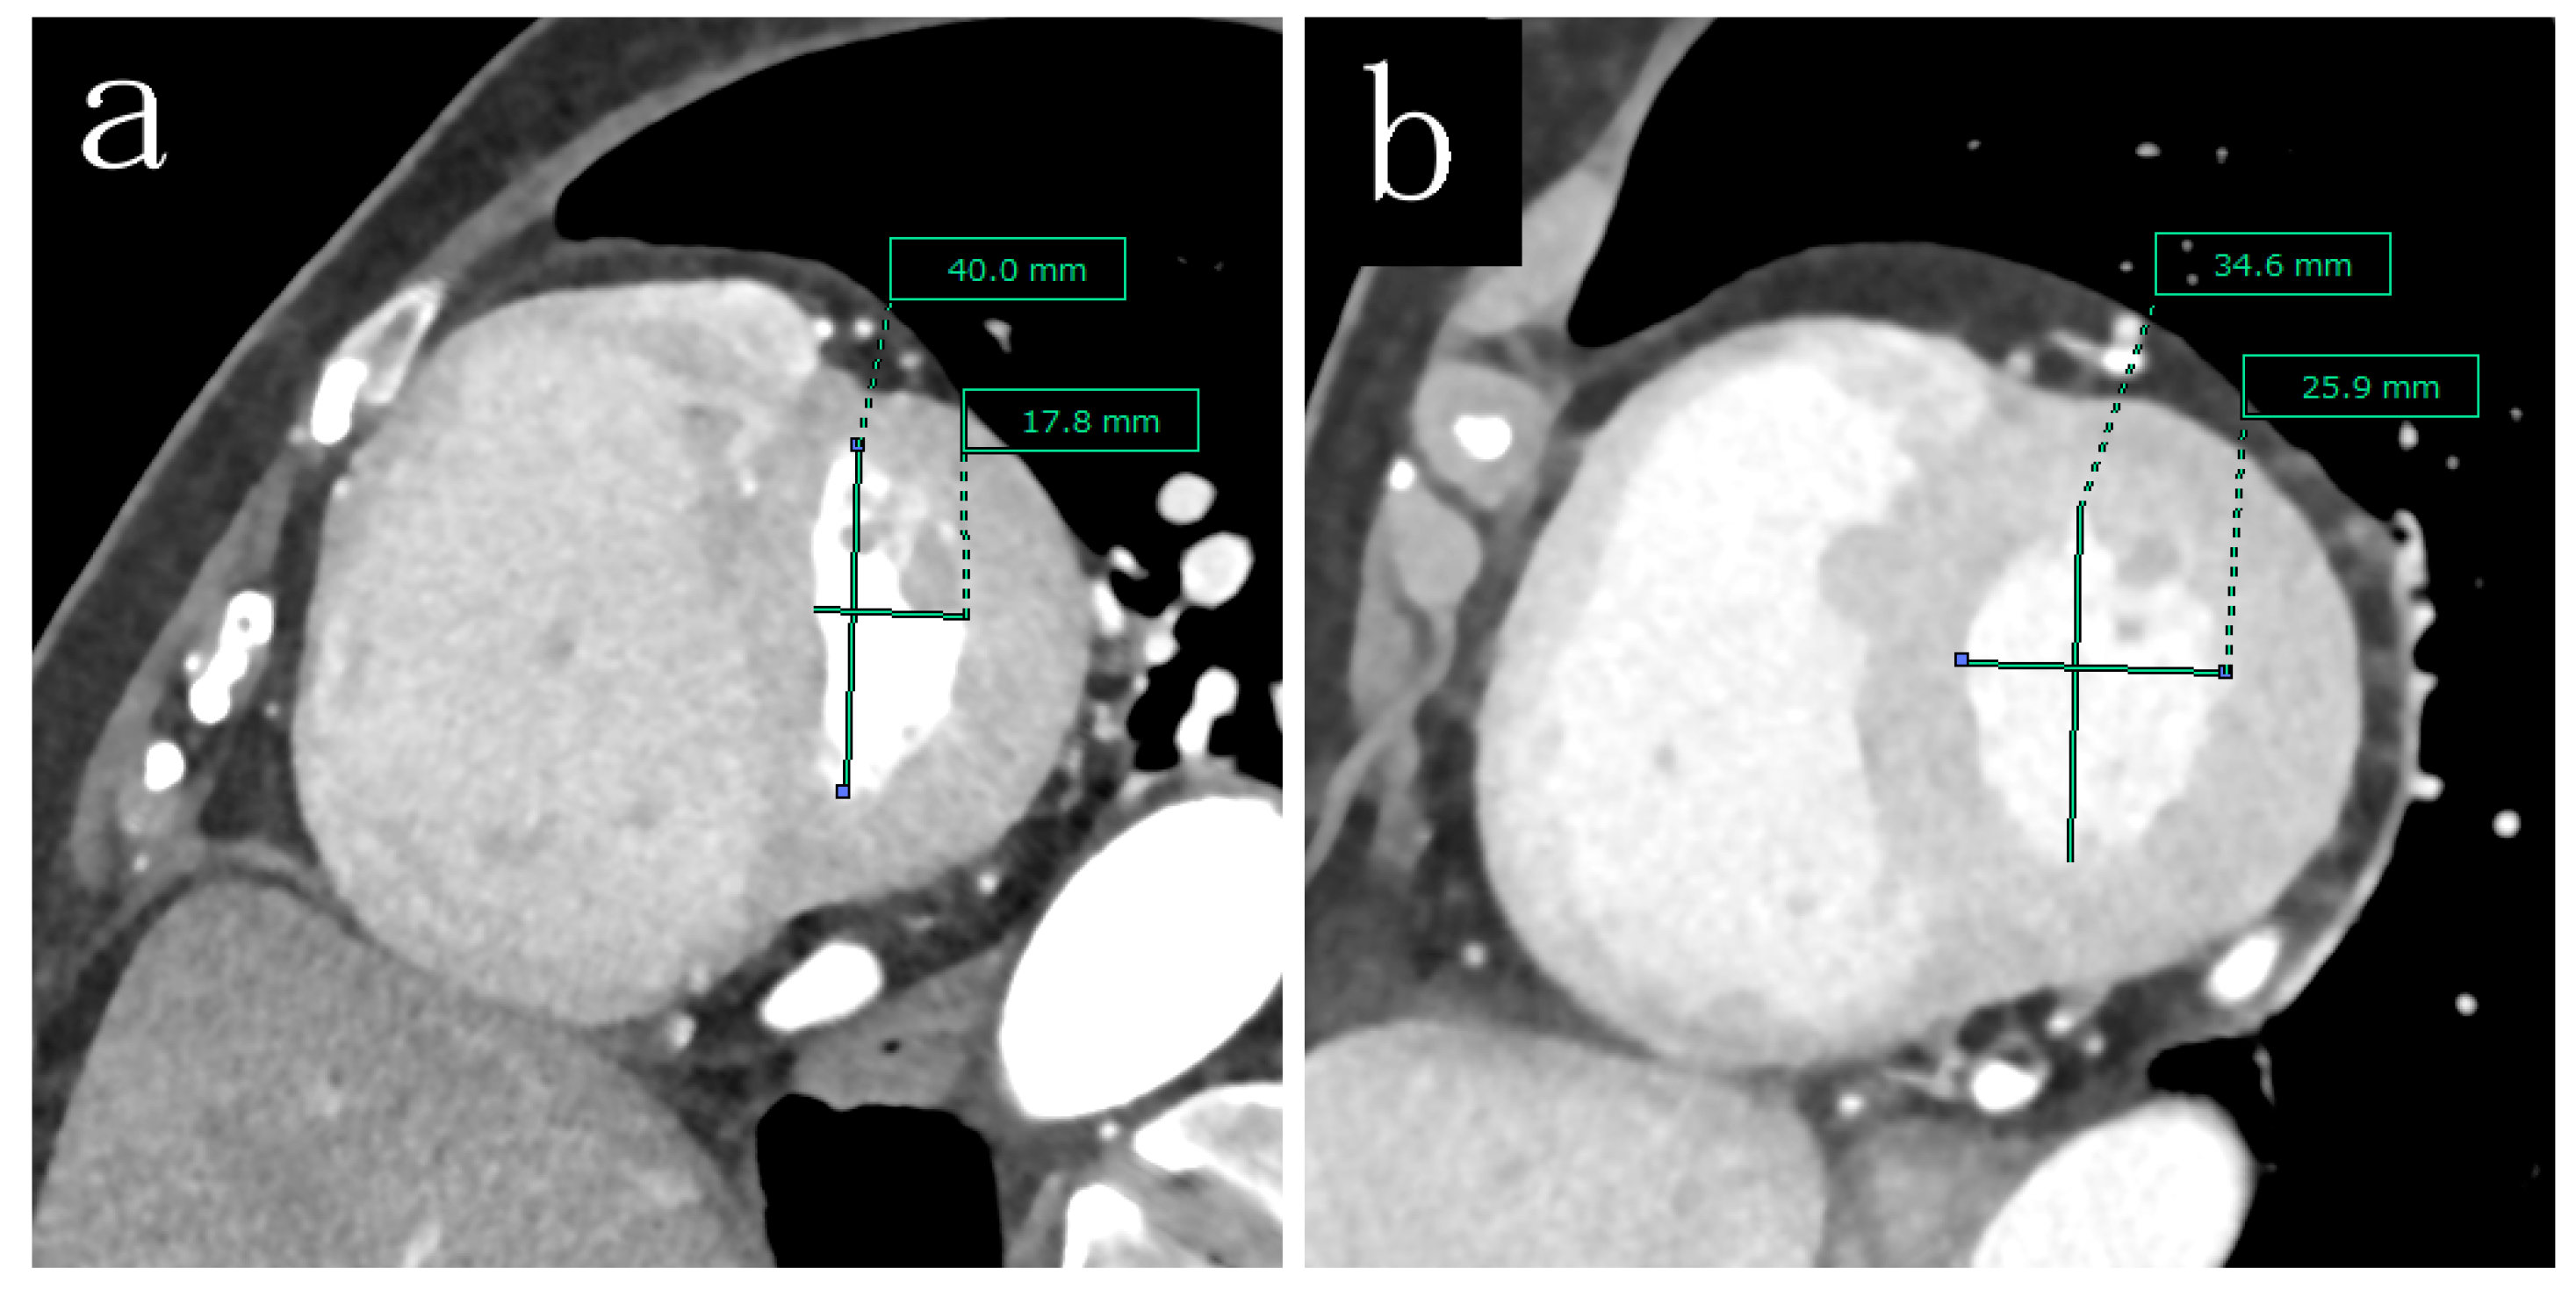

To estimate the factors related to the esEI, the patients’ characteristics were compared between the high and low esEI groups (Table 4). Figure 2 shows the representative short axis images of the left ventricles in case of different esEI. The 6MWD was lower (p = 0.017) and brain natriuretic peptide (BNP) levels were higher (p < 0.001) in the high esEI group than in the low esEI group. The systolic pulmonary arterial pressure (p < 0.001), diastolic pulmonary arterial pressure (p < 0.001), mPAP (p < 0.001), right atrial pressure (p < 0.023), and PVR (p < 0.001) were significantly higher in the high esEI group than in the low esEI group. Volumetric-enhanced MDCT revealed that the RVEDV (p < 0.001) and RVESV (p < 0.001) were larger, whereas LVCO (p = 0.003) were smaller in the high-esEI group than in the low-esEI group. The RVEF (p < 0.001) and LVEF (p = 0.013) were lower in the high esEI group than in the low esEI group. Furthermore, the independent factors related to the esEI were the RVESV (p = 0.001), LVCO (p = 0.038), and LVEF (p = 0.033) in multivariate analysis (Table A1).

Figure 2. Representative short axis images of the left ventricles in case of different esEI. (a) high esEI case, (b) low esEI case.